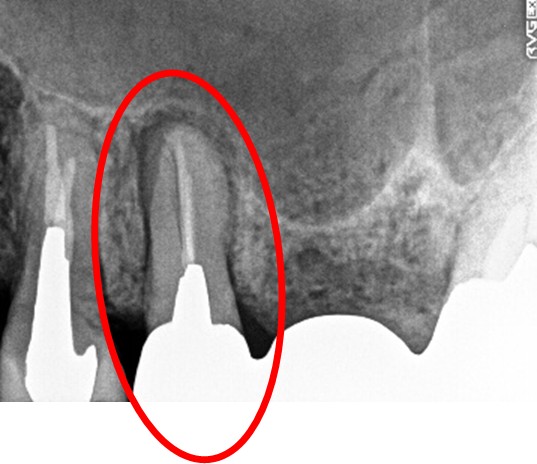

女性Hさん 60代(オールセラミック冠・インプラント)

主訴

右下のブリッジがゆらゆら動く。

治療内容

ブリッジの支台になっている奥の歯が、被せ物の中で虫歯になり、支台の役割を果たさず、前方の歯のみで支えられていました。前方の歯をそのままにして、後方の部分を切り離すと、そのまま取れてきました。中は、虫歯で歯根しか残っていない状況でした。この歯は、根管治療後、単独でオールセラミック冠を被せ、歯のないところにインプラントを埋入しました。

Before

冠の中で大きな虫歯になり支台の役割を果たしていませんでした。

【インプラント埋入前】

冠はブリッジを切断しただけで取れてきました。軟化象牙質を取り除いたところ、歯根しか残っていない状況で保存できるかどうかのぎりぎりのところでした。